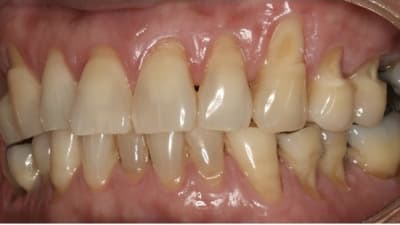

Oral Health Insights Periodontics Oral Surgery Enhancing Esthetic Outcomes Through Periodontal Plastic Surgery By P.D. Miller, DDS, Peter Nordland, DMD, Robert A. Levine, DDSDDS March 01, 2018 4 min read